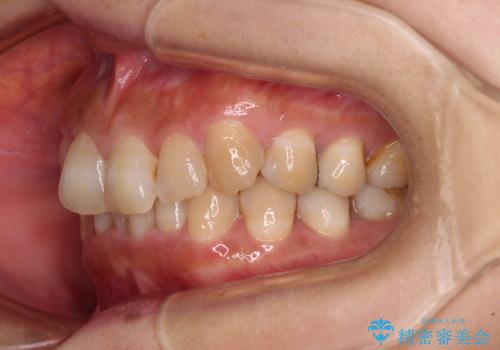

ディープバイトと前歯のデコボコ インビザラインによる矯正治療

- 前歯のディープバイトと叢生を気にして来院された患者様です。

目立ちにくい装置を希望されていたため、ワイヤー装置とインビザラインを提案したところ、インビザラインを希望されました。

下顎大臼歯が手前に倒れていたため、起き上がらせることで咬み合わせ高さを挙上し、ディープバイトと叢生を改善することとしました。